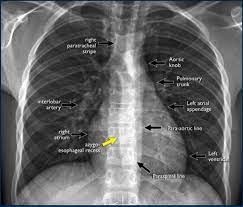

4. Imaging in Surgery: X-Ray Interpretation Made Easy By Dr. Amrit Nasta

Image-based questions are now standard in NEET SS, FMGE, and surgical vivas. This lecture equips you with a step-by-step method to confidently handle X-ray-based questions.

📌 What You’ll Learn:

• How to describe any surgical x-ray: From top to bottom — lines, shadows, foreign bodies, everything.

• PA vs AP views: Know how positioning affects interpretation.

• Common x-rays in surgery: GI perforation, chest x-ray, contrast studies, foreign body cases.

• How to think like an examiner: What they want to hear in a viva.

If you fear X-ray interpretation, this video is your shortcut to mastery.